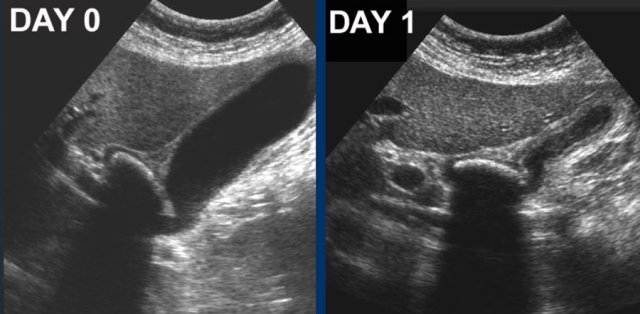

At day 0 there is acute hydrops due to an impacted stone.

One day later, the patient is symptom free.

The stone is still in place, but apparently allows passage of bile to the cystic duct, since hydrops has disappeared.

Reperfusion edema and sludge are the silent witnesses of the previous attack .

CRP remained normal.